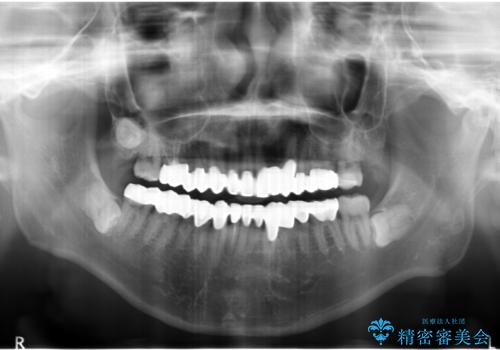

歯頚ラインが変えられないことや天然歯を削るリスクをご理解頂いた上で、オールセラミッククラウンによる補綴治療を行いました。(見えない奥歯のみ天然歯のままとしました)

下の前歯1本だけ歯軸を変えるために神経をとり根管治療を行っております。

- ¥2,790,000 (仮歯×24本、根管治療×1本、土台×1本、クラウン×24本、セラミックインレー×1)費用は治療当時の料金となります

クラウンの色味・形態の修正や患者様のお仕事のご都合で来院できない期間があったことにより、予想より治療期間が長くなってしまいましたが、審美的な仕上がりにご満足頂けました。

クラウンの色味に関して、自然な白さ(シェードA1~NW0.5)のクラウンを作製・試適したところ「もっと白くしたい」と希望され、当院で最も明度の高い色(シェードNW0)に修正しました。

被せ物の種類:オールセラミッククラウン スタンダード (シェード:NW0)